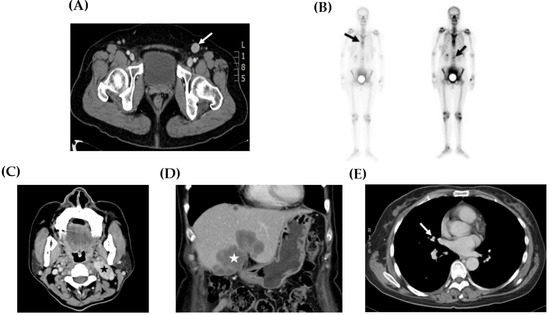

| Recurrent/metastatic site | Inguinal LN, bone | Inguinal LN | No recurrence | NA a | Abd. wall, inguinal LN, neck LN, liver, lung | Abd. wall, inguinal LN |

| Salvage treatment | - | Tumor excision | - | - | Chemotherapy b + Radiotherapy c | - |

| DFS (m) | 10 | 3 | 93 | NAa | Progression | Progression |

| OS (m) | 14 | 11 | 97 | 5 | 23 | 7 |

| Current status | Recurrence | NED | NED | NED | DOD | Progression |